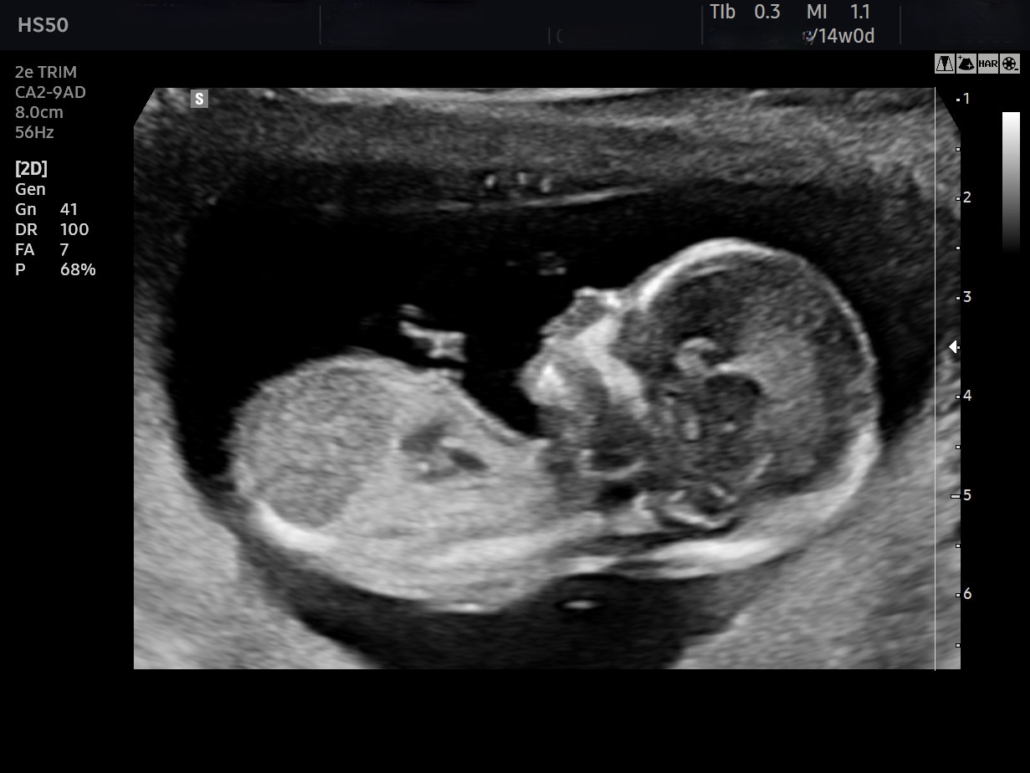

Een echo, of echografie (klinkt gelijk een stuk wetenschappelijker, hè?), is een specifieke soort scan. Het gebruikt geluidsgolven om een beeld te vormen. Denk aan een sonar op een onderzeeër die objecten opspoort. Ze sturen een geluidspuls uit en wachten tot die terugkaatst (de echo!), om te bepalen hoe ver iets weg is en hoe het eruit ziet.

Het fijne van een echo is dat het geen schadelijke straling gebruikt. Daarom is het zo populair tijdens de zwangerschap. Stel je voor dat je je baby kunt zien groeien, zonder dat je je zorgen hoeft te maken over röntgenstraling! Het is net als een sneak peek trailer van een film, maar dan van je eigen kind.

Maar het is niet alleen voor zwangere vrouwen! Echo's worden ook gebruikt om allerlei andere dingen te bekijken, zoals je hart, je lever, je nieren en je bloedvaten. Een dokter kan bijvoorbeeld zien of je galstenen hebt of dat er iets mis is met je schildklier.